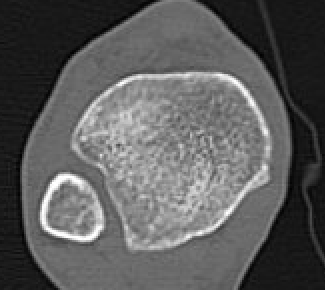

CT

Normal bilateral axial CT

Bilateral axial CT

- compare to other side

- widening

- malrotation

- posterior malleolar fracture / Volkmann tubercle

- anterior tubercle / Tillaux-Chaput tubercle

Gifford's tibiofibular line (TFL)

- anterolateral fibula

- should be < 2 mm from tibia

< 4 mm Tibio-fibular gap

Abormal Gifford's line and increased tibiofibular gap with posterior malleolar fracture